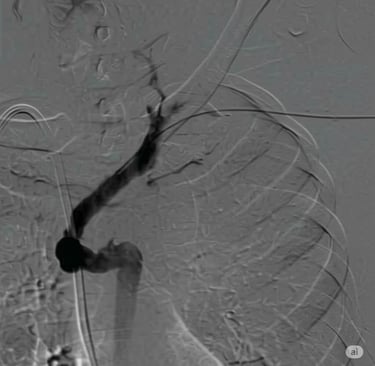

Flebografía de vena cava superior estenótica

Paso de guía Amplatz Super Stiff por zona de estenosis dentro de la vaina de fibrina